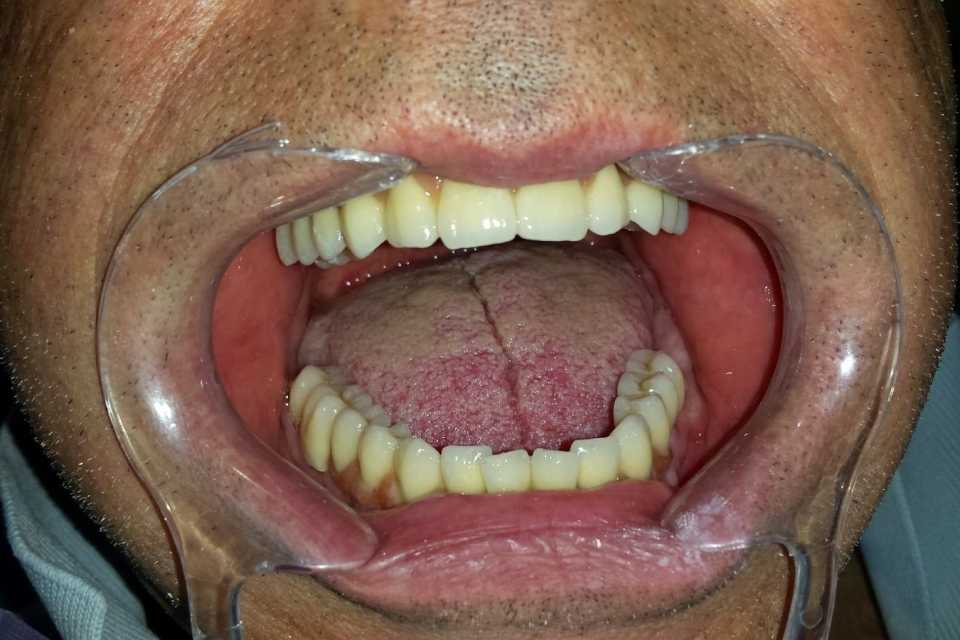

Pacientul s-a prezentat în cabinet cu o edentație totală bimaxilară. Au fost inserate 8 implanturi la maxilar și 8 implanturi la mandibulă. După perioada de osteointegrare au fost făcute două punți totale metalo-ceramice (ceramica Ivoclar D'sign).